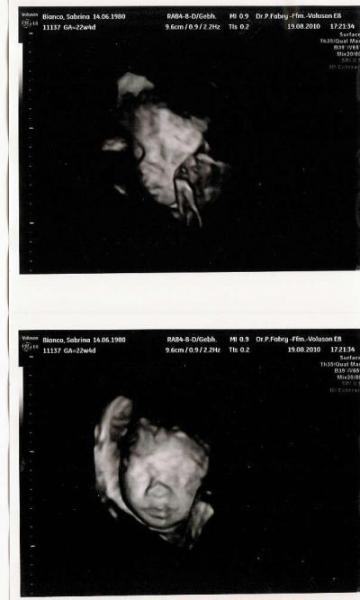

Hallo zusammen, ich bin nicht so der aktive Schreiber, eher ein stiller Leser aber ich hoffe dass ich trotzdem hier jederzeit willkommen bin. Letzten Donnerstag war ich wieder mal bei der VU und dem Baby geht es hervorragend. Alles war wunderbar. Der FA hatte mir auch 2x zu 99,9% bestätigt dass es wieder ein Mädchen wird. Leider habe ich es nicht gesehen aber ich vertraue ihm, da er bei meinen anderen 2 auch immer richtig lag. Möchte euch noch gerne das tolle Ultraschallbild von der kleinen Maus zeigen. Jetzt müssen wir uns nur noch auf einen Namen einigen. LG Sabrina

Bild zu Auch mal melden...! - Forum für Dezember - Mamis

wow,tolle bilder, ich möchte auch endllich von unserer maus ein 3d bild haben, aber letzte woche hatte sie beide arme direkt vor dem gesicht, bis zum nächsten termin sind es jetzt noch 3 wochen hoffe dann hab ich auch mal glück.

Schöne 3 D Bilder, ich gehe am 18.09 zum 3 D und hoffe meine kleine spielt mit, da es eine kostenlose Aktion beim Tag der offenen tür im KH ist, das wäre schon klasse. lg